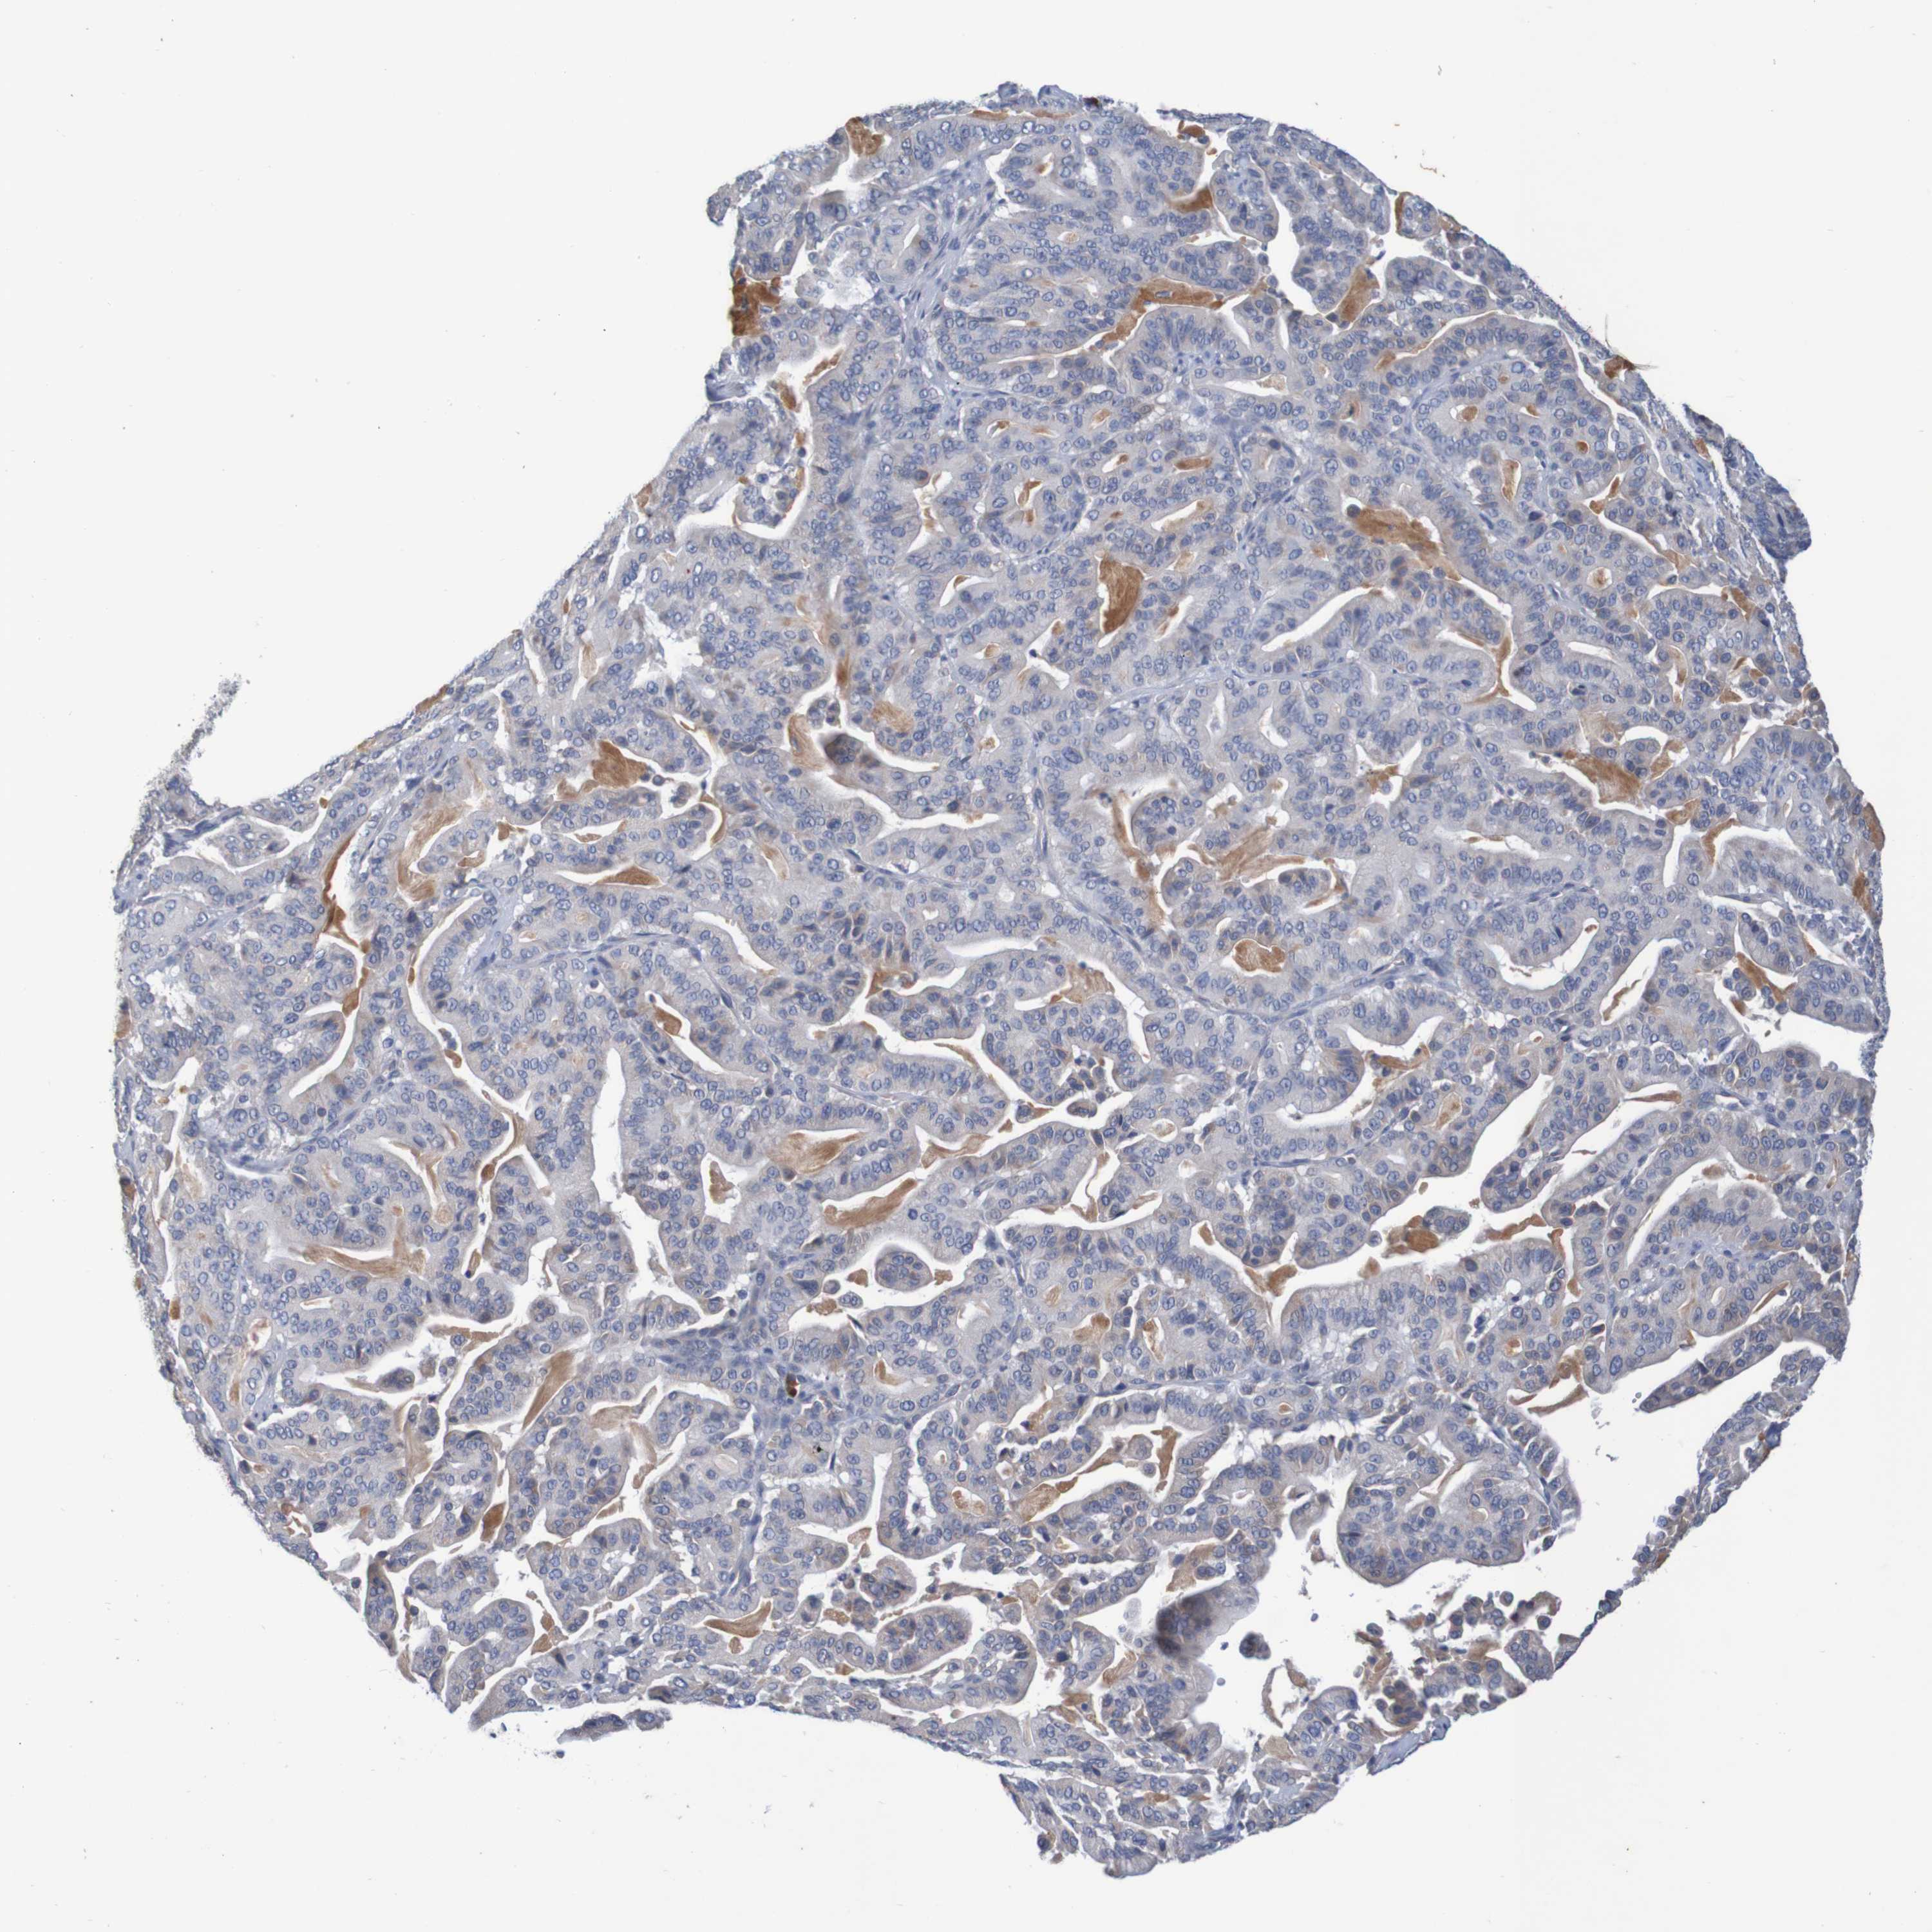

PANCREATIC CANCER - Protein expressioni

A mouse-over function shows sample information and annotation data. Click on an image to view it in a full screen mode. Samples can be filtered based on level of antibody staining by selecting one or several of the following categories: high, medium, low and not detected. The assay and annotation is described here.

Note that samples used for immunohistochemistry by the Human Protein Atlas do not correspond to samples in the TCGA dataset.

Antibody stainingi

Antibody staining in the annotated cell types in the current human tissue is reported as not detected, low, medium, or high, based on conventional immunohistochemistry profiling in selected tissues. This score is based on the combination of the staining intensity and fraction of stained cells.

Each image is clickable and will lead to virtual microscopy that enables deeper exploration of all samples and also displays staining intensity scores, fraction scores and subcellular localization as well as patient and tissue information for each sample.

Antibody HPA007729

Staining

High

Medium

Low

Not detected

Intensity

Strong

Moderate

Weak

Negative

Quantity

>75%

75%-25%

<25%

None

Location

Nuclear

Cytoplasmic/membranous

Cytoplasmic/membranous,nuclear

Adenocarcinoma, NOS

Adenocarcinoma, metastatic, NOS